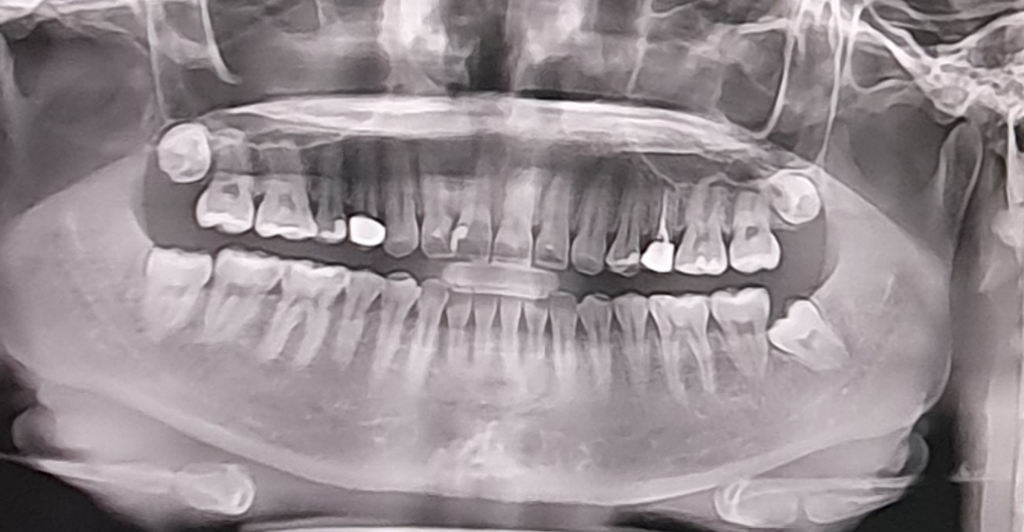

사랑니 발치 어려운 경우인가요?

안녕하세요! 자꾸 글올려서 죄송합니다 낼 상악 사랑니 뽑으러가는데 벌써부터 무섭네요. 왼쪽하악은 신경이랑가깝다고햇는데도 10분도안걸렸거든요.. 제 사랑니 4개가 모두 까다로운 케이스인가요? 특히 상악이 어떤지 궁금합니가!

• 1번 째 사진

크게 어려워보이지는 않으나 사랑니는 변수가 많아 발치를 해봐야 난이도를 알 수 있기도 합니다

사랑니가 크게 어려운 케이스는 아닌거 같습니다. 그나마 까다로운게 왼쪽아래사랑니 같은데 그거 빼셧다면 다른곳은 크게 걱정하지 않으셔도 될것같습니다.

상악 사랑니의 경우 하악에 비해 뼈가 무르고 발치 공간이 넓어 하악에 비해 발치가 간단하며

사진 상 크게 난이도가 있는 상태는 아니므로 걱정 안하셔도 괜찮습니다